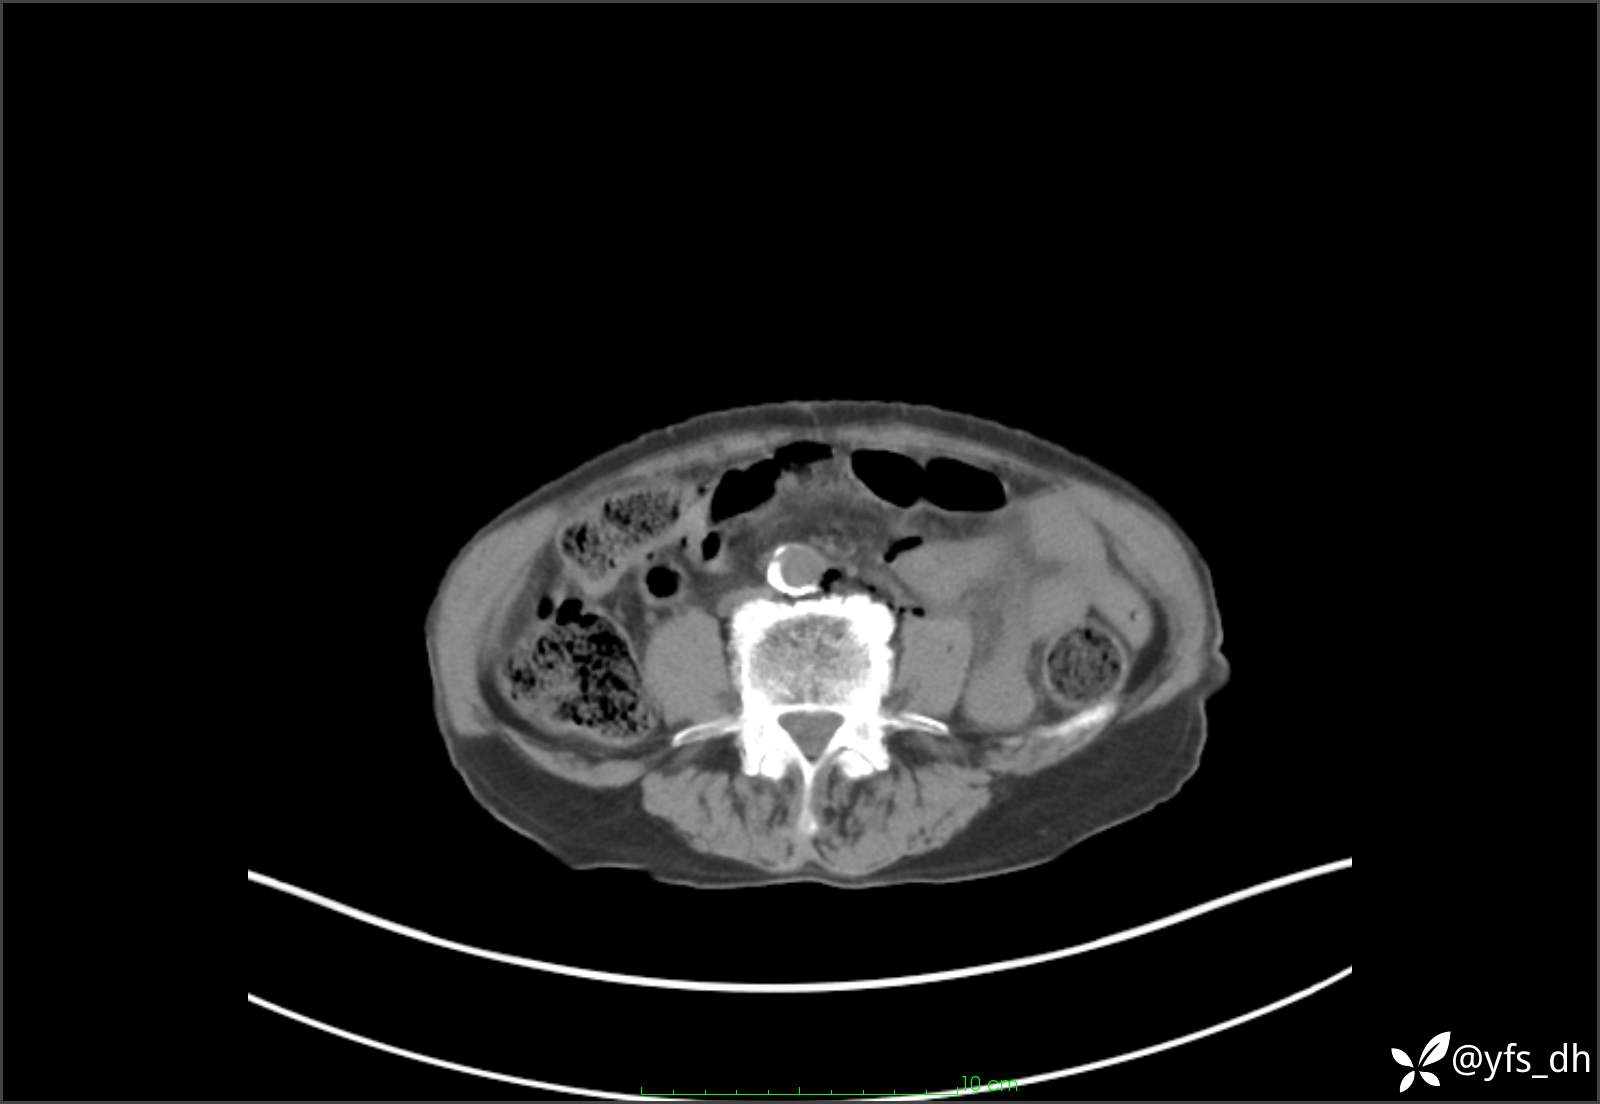

1.简要病史:患者4天前突发上腹部疼痛不适,但可以忍受。3小时前饭后突然加重,不能忍受后就诊。

2.简要手术记录:术中见腹盆腔大量肠液及粪便,乙状结肠中下段见一约3cm的破口。